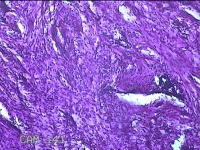

前胸部包块

性别

女

年龄

45岁

临床诊断

皮脂腺囊肿

一般病史

发现前胸部包块3个月余。

标本名称

大体所见

灰白暗红色组织2.2x1x0.8cm一块,表面带梭形皮肤2.2x1.3cm,皮下见包块1.8x1.2x0.8一块,切开包块呈实性,切面灰白粉红色,质软。